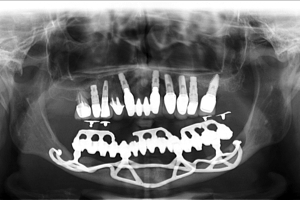

Figuras 5 e 6 – Aspecto clínico e radiográfico de reabilitação com implantes osseointegrados superiores e subperiósteos (justaósseos) inferiores. Estes com 30 anos de função.